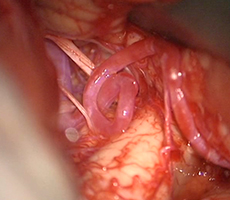

[手術方法]

-

頭皮の血管(浅側頭動脈)

頭皮の血管を脳表の血管に吻合します。

実際の手術

浅側頭動脈と脳表の血管 -

頭皮と脳表血管の吻合 -

術中蛍光撮影でバイパス血流の確認 -

脳表を筋肉で覆う。